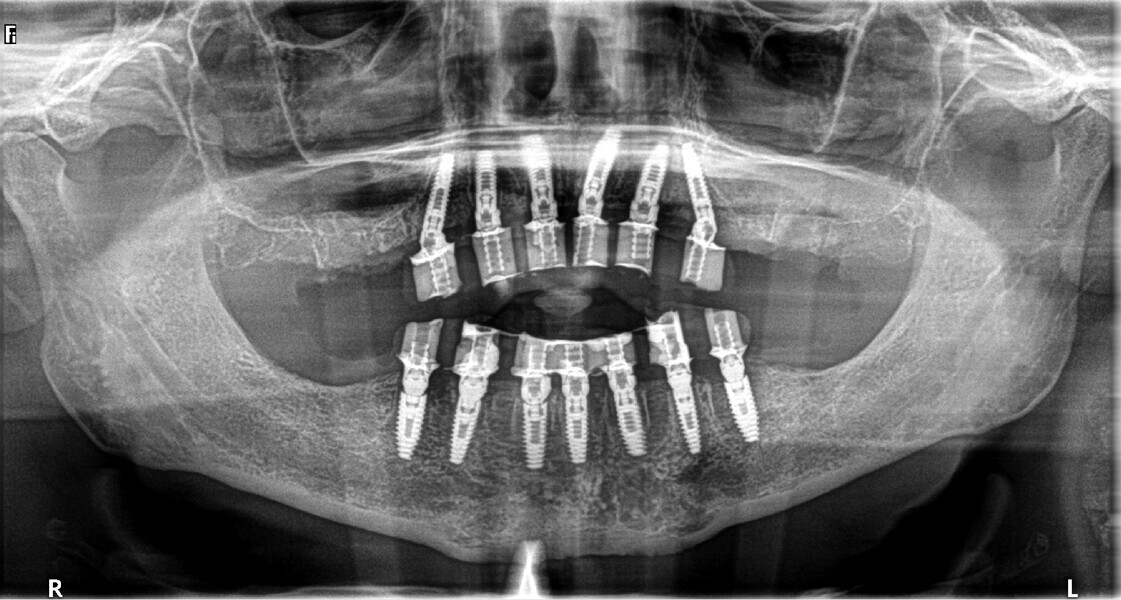

Fig. 20: Post-op panoramic view.